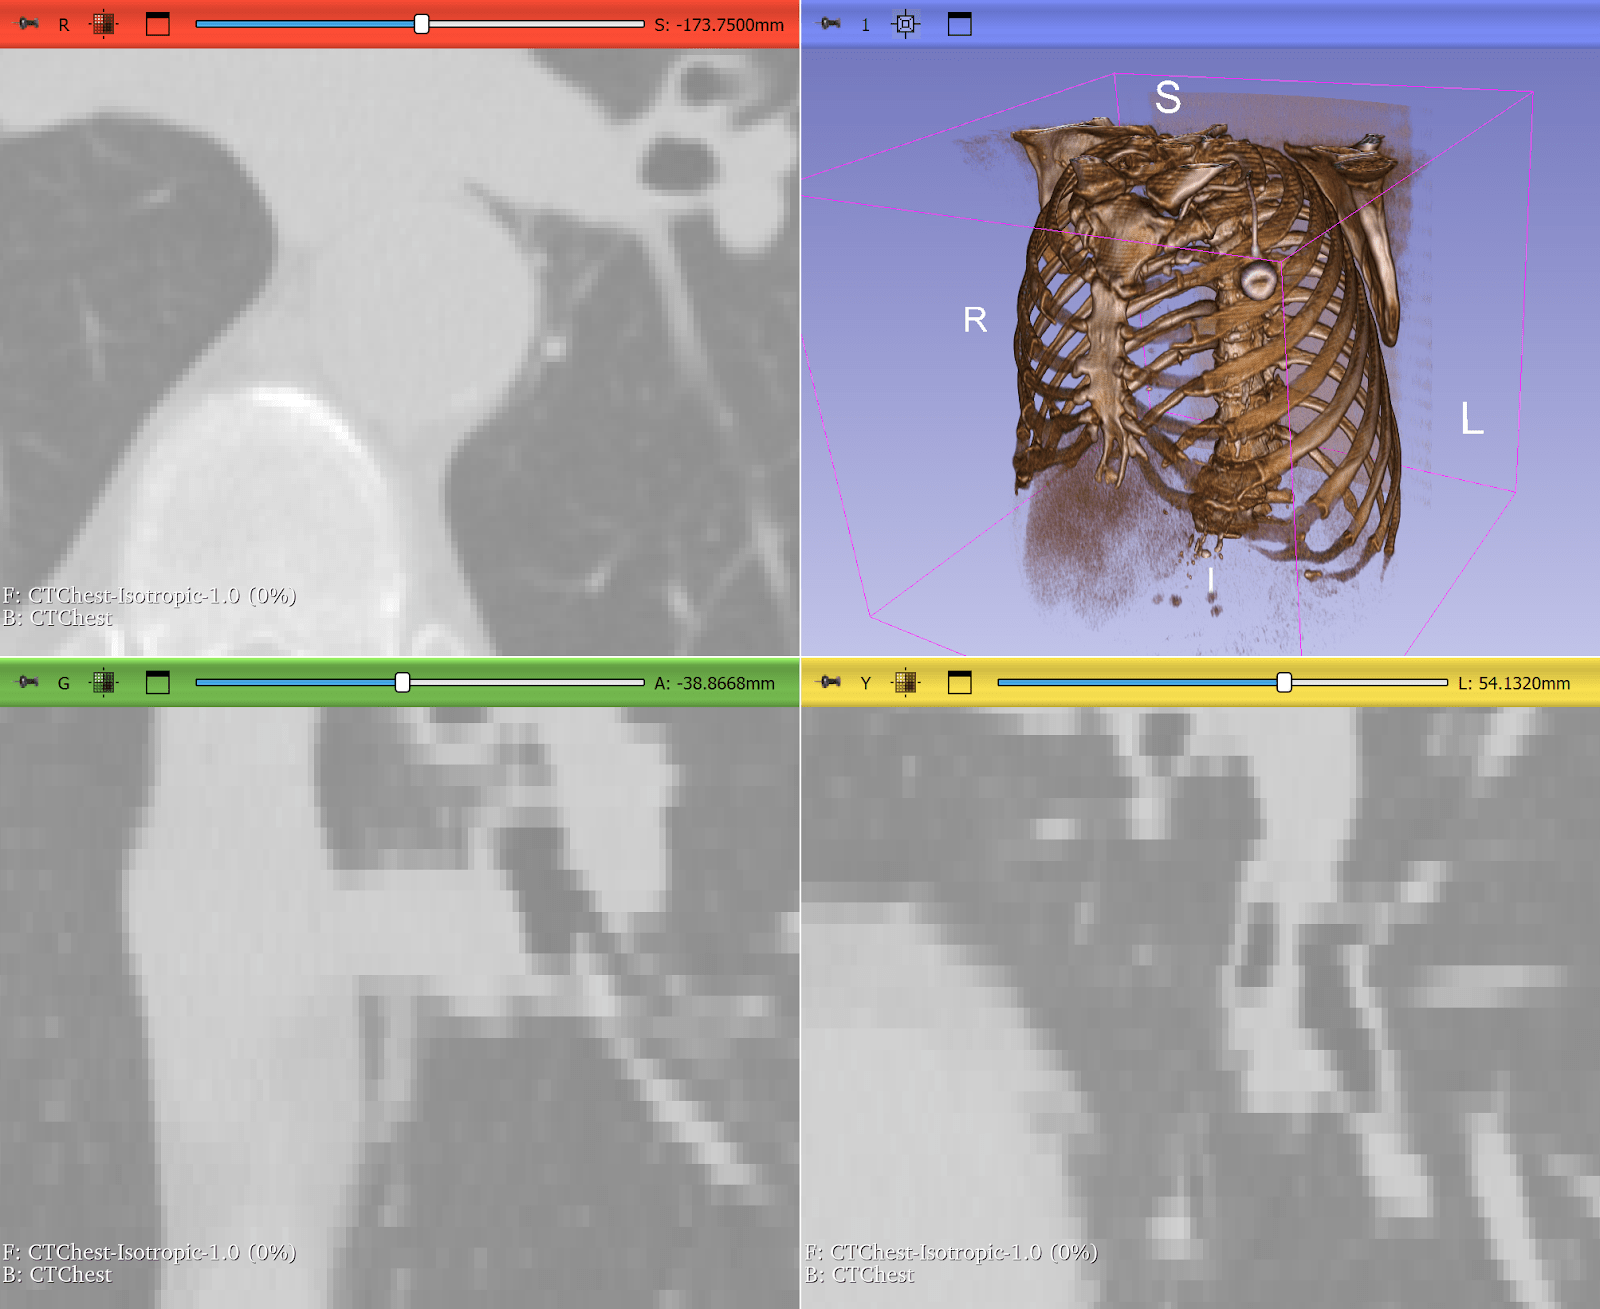

Resampling Lung CT Scans to Isotropic Voxels

Computed tomography (CT) scans often have anisotropic voxel spacing where the resolution along the axial slice direction is coarser than in-plane resolution. Deep learning models, especially 3D CNNs, perform poorly on such inconsistent geometry.

ITK provides robust resampling via the ResampleImageFilter, allowing researchers to convert CTs into isotropic voxel spacing (e.g., 1×1×1 mm³). This makes it quicker and easier to train deep learning models across heterogeneous datasets. In some cases, it can be as simple as:

This step is widely used in lung segmentation and COVID-19 CT analysis pipelines, where consistency in voxel geometry is critical for accurate volumetric measurements and model performance.

Figure 3: Lung CT before and after resampling, zoomed in with nearest neighbor resampling to show voxel sizes. Before: voxel size 0.76 x 0.76 x 2.5 mm. After: 1x1x1 mm. Use left-right slider to compare before vs. after.